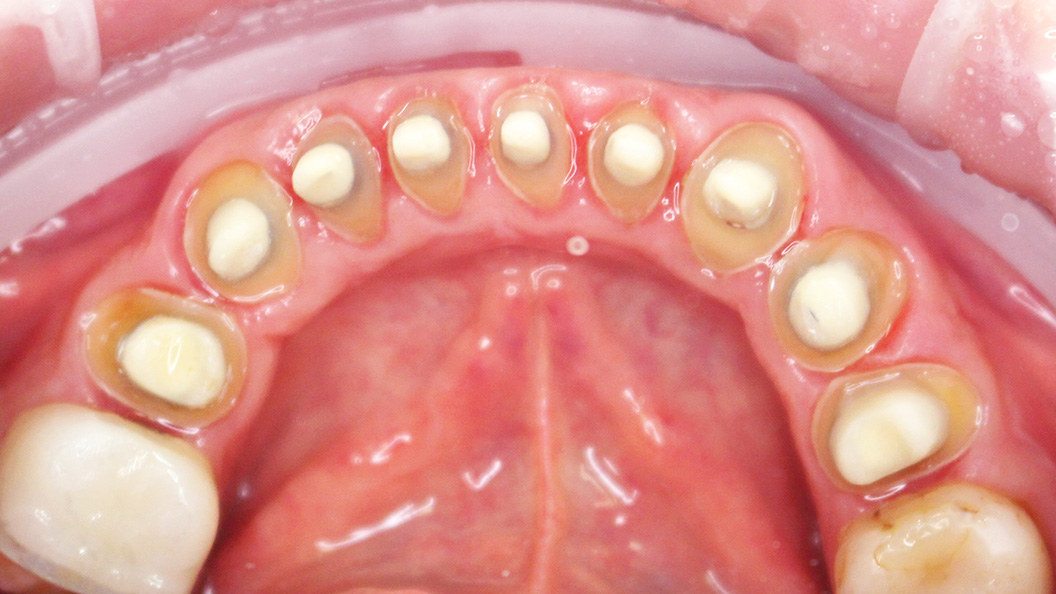

В нашу клинику обратился пациент с жалобами частично-разрушенные зубы нижней челюсти.

На момент осмотра была выявлена необходимость в протезировании 9-ти нижних зубов.

В ходе процедуры были проведены следующие работы:

- профессиональная гигиена полости рта;

- пролечивание зубов и укрепление их культевыми вкладками с керамической облицовкой;

- снятие слепков с обеих челюстей;

- установка диоксид-циркониевых коронок на зубы 35-44.